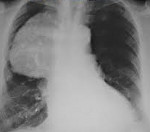

Ведущая роль в диагностике кист средостения принадлежит рентгенологическим исследованиям. Полипозиционная рентгеноскопия и рентгенография грудной клетки, рентгенография пищевода и сердца, пневмомедиастинография позволяют определить локализацию, форму и размеры кисты, ее связь с соседними органами, изменение положения при дыхательных движениях. Для более детальной оценки структуры, толщины стенок кисты, характера содержимого и взаимоотношения с соседними анатомическими образованиями, производится КТ и МРТ средостения.